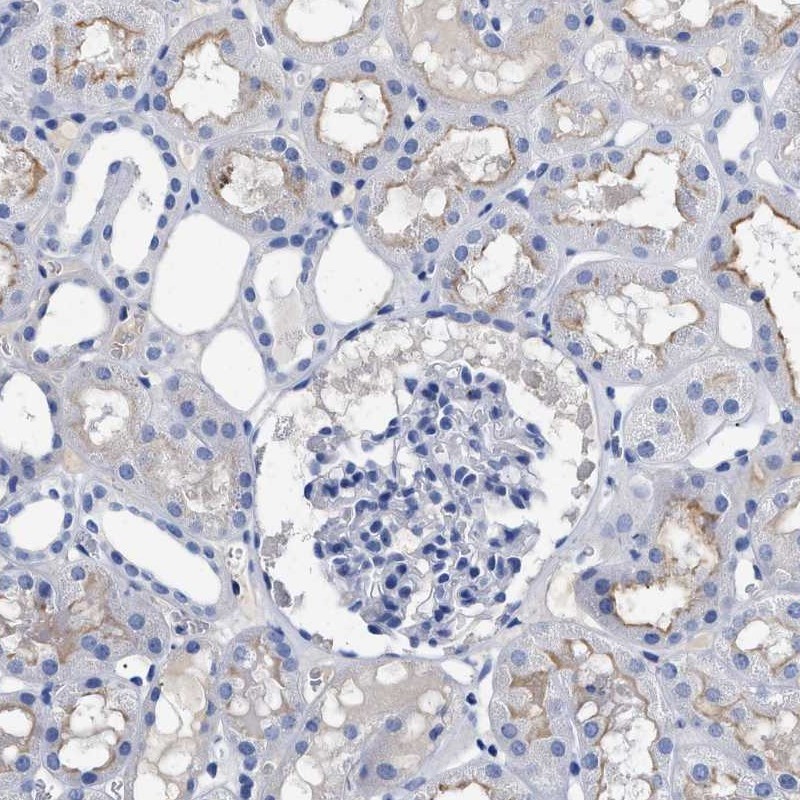

Immunohistochemistry analysis in human smooth muscle and kidney tissues using Anti-ACKR1 antibody. Corresponding ACKR1 RNA-seq data are presented for the same tissues.